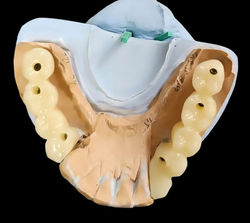

ВАЖНО! В нашей клинике человеческий фактор полностью нивелируется посредством навигационной хирургии и использованием цифрового протокола лечения. Этот протокол предусматривает сбор и анализ рентгеновских снимков и моделей полости рта пациента с переводом этих данных в цифровой вид. Это позволяет планировать реализацию постановки импланта и вид будущей коронки еще до этапа имплантации.